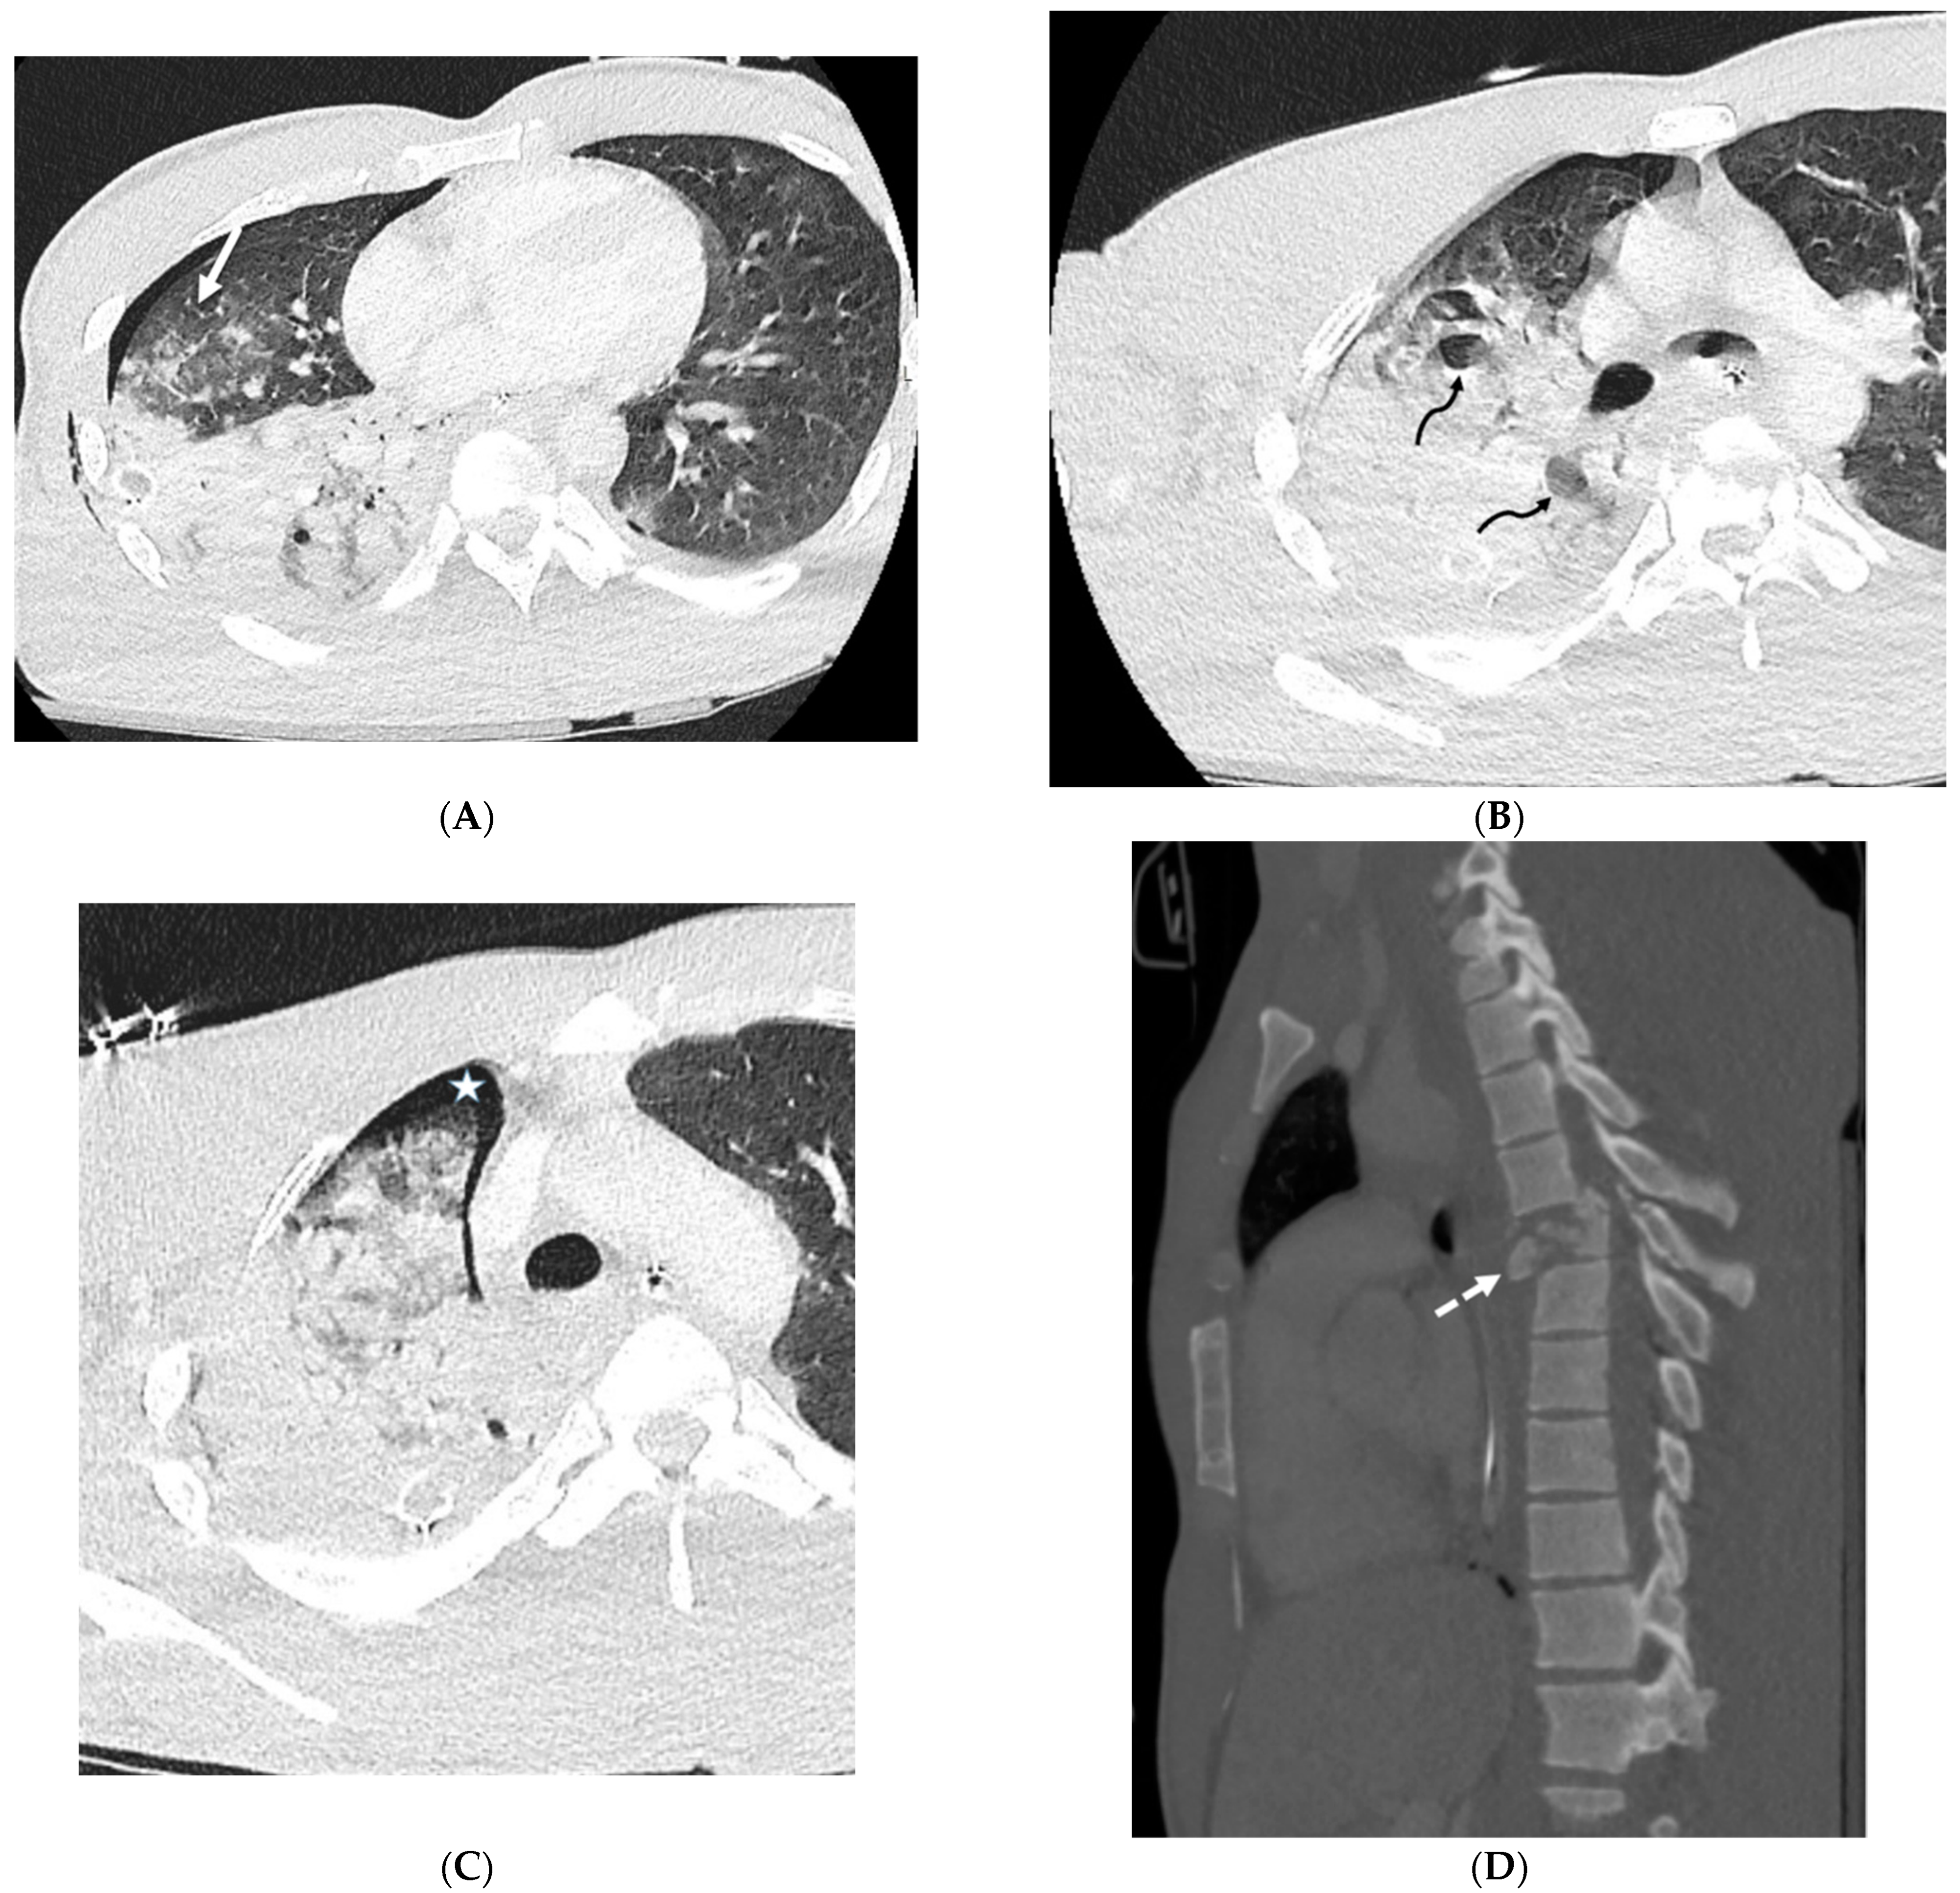

| Silicone embolization | History of illegal cosmetic injection of liquid silicone | Multiple subcutaneous soft tissue attenuation nodules, sometimes with peripheral calcification or surrounding fat stranding |